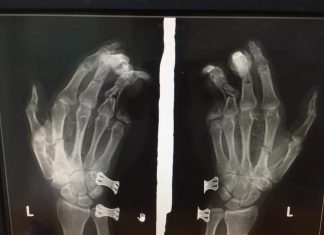

Bảo Lộc: Điện thoại phát nổ, nam thanh niên bị dập nát bàn tay

Nam thanh niên đang sử dụng điện thoại vừa cắm dây sạc vừa chơi game thì điện thoại phát nổ khiến bàn tay trái bị dập nát, ngón út bị cụt mất 2 đốt.